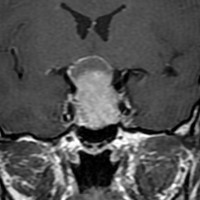

典型的なMRIの画像です

下垂体腺腫のMRIです。両側の視野障害(両耳側半盲)のために手術を受けた患者さんのものです。この腫瘍は非機能性腺腫といってホルモンを出さない腫瘍でした。少し大きめでしたが全部取れて視野の障害はよくなりました。

左の2枚はガドリニウム造影剤を使って写したもので腫瘍の形がよくわかります。右の1枚はT2強調画像と言います。MRIでは撮影の仕方によって見え方が違います。